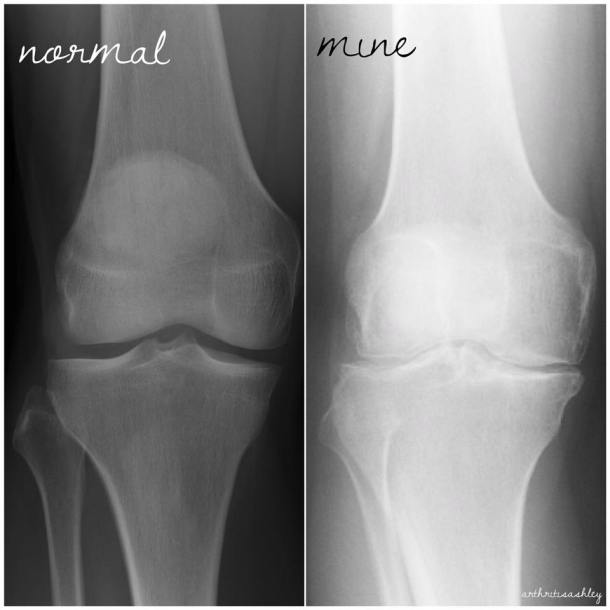

I thought I’d share these as a follow-up to my “My Joints are 90 Years Old” post.

I am having a total knee replacement of the right knee in a few weeks.

I’ve been told that my joints look 80 or 90 years old!

How can you tell? Compare joint space, shape, white areas. JIA, RA, and OA have ravaged the joints.